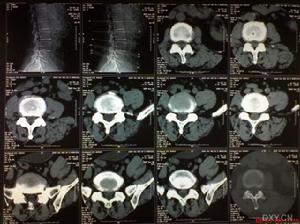

1、正確使用影像學檢查:MR I檢查是當前診斷椎管內腫瘤的重要手段,文獻報導其術前定位診斷準確率 97.1%,定性診斷準確率70.6%,發病部位、信號強度及強化特徵是MR I診斷椎管內腫瘤最重要的依據。CT 診斷腰椎間盤突出症準確率在80.0% ~93.2%,但因其斷層面有局限性,可出現假陽性和假陰性。溫新東等對200例腰腿痛患者行MR I及CT檢查,其中42 例腰椎管內腫瘤CT檢查均漏診或誤診。故對有不典型臨床表現的腰腿痛患者,應警惕腰椎管內腫瘤,術前必須行MR I檢查助診,必要時做腦脊液和脊髓造影檢查。

2、提高腰椎間盤突出症合併椎管內腫瘤的認識: 腰椎間盤突出症合併椎管內腫瘤從症狀和體徵與單純腰椎間盤突出症不易鑑別,本組有28例行MR I檢查前均漏診腰椎管內腫瘤。CT檢查往往只掃描椎間盤平面,孤立的椎管內腫瘤容易漏診。總之,對於頑固性下腰背部痛伴根性神經疼痛者,應想到二者並存的可能, 完善X線、CT、MR I檢查,及早手術以免延誤病情。

2.CT檢查椎體的腫瘤(如動脈瘤樣骨囊腫、嗜酸性肉芽腫脊索瘤、骨巨細胞瘤等)多見椎體塌陷、骨質廣泛性破壞,出現低密度病變區周圍可見高密度成骨反應或鈣化;多有椎體膨脹和邊界不清的軟組織腫塊影,向椎管內發展時可見脊髓的受壓移位。髓內腫瘤(室管膜瘤、星形細胞瘤成血管細胞瘤等)多見脊髓的局限性增粗脹大伴有脊蛛網膜下腔或硬膜外間隙的變窄腫瘤密度均一,多為低或等密度少數為高密度腫瘤與正常脊髓界限不清,可增強或不增強髓外硬膜下腫瘤(神經纖維瘤脊膜瘤、脂肪瘤和腸源性囊腫)可因不同腫瘤的類型表現各異神經纖維瘤多呈等或稍高密度,有囊變和鈣化,中等均一強化可因腫瘤的椎管外生長導致椎管或椎間孔的擴大,多見椎管內外相連的“啞鈴”型腫塊影;脊膜瘤多為高密度,明顯均一強化;脂肪瘤多呈分葉狀低密度腫塊不強化;椎管內腸源性囊腫多位於頸胸髓的腹側邊界規則清楚呈囊性信號不強化或僅包膜輕度強化;但髓外硬膜下腫瘤有一共同的特徵是:脊髓密

度多正常,以受壓移位改變為主,可見腫瘤上下蛛網膜下強的擴大而在腫瘤平面則變狹窄或消失。硬脊膜外腫瘤見椎管內邊緣銳利的軟組織腫塊影硬脊膜囊受壓脊髓呈淺弧形移位,相鄰骨質可有破壞。

3.MRI檢查脊髓的MRI矢狀位成像可不受脊椎生理彎曲的影響,充分連續的顯示脊髓的全長及椎管前後緣的關係更好的確定病變的解剖界限;冠狀位可觀察脊髓兩側的神經根和脊髓的形狀,以鑑別髓內髓外病變及其範圍(圖23);而且MRI對脊髓內病變的信號特徵顯示也優於CT是椎管內病變的首選檢查措施.

陳女士,五年前開始出現左腿疼痛,之後疼痛逐漸加重,上居住地醫院進行過腰椎CT檢查,開始被診斷為“腰椎間盤突出症”。可治療很長時間,病情反而加重,劇烈的腿痛常使她輾轉反側、夜不能寐。後來,她轉到廣州中醫藥大學第一附屬醫院脊柱專科,醫師給她進行了MRI檢查(核磁共振造影)等系統的檢查後,最終確診為“椎管內腫瘤”。手術把腫瘤切除後,腿痛隨之消失。